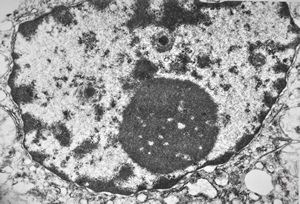

M,5y. | activated nucleolus - Reye hepatocerebral syndrome